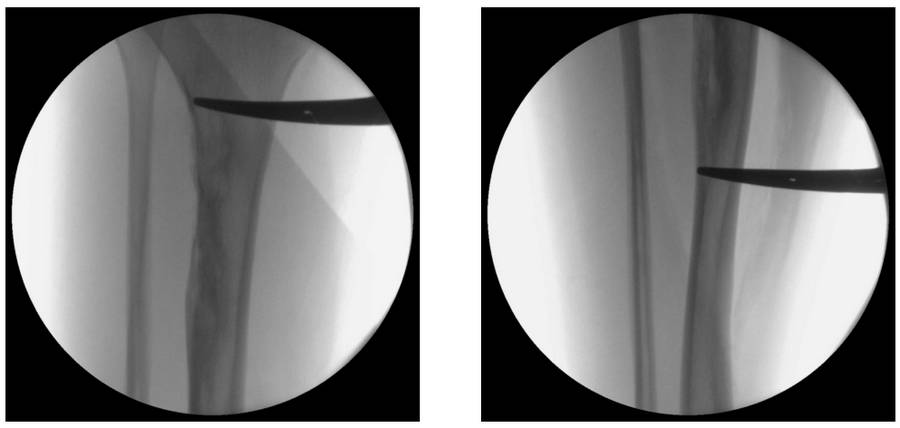

Ameliyat Esnası: Skopide kitlenin proksimal ve distal sınırı işaretlenmekte